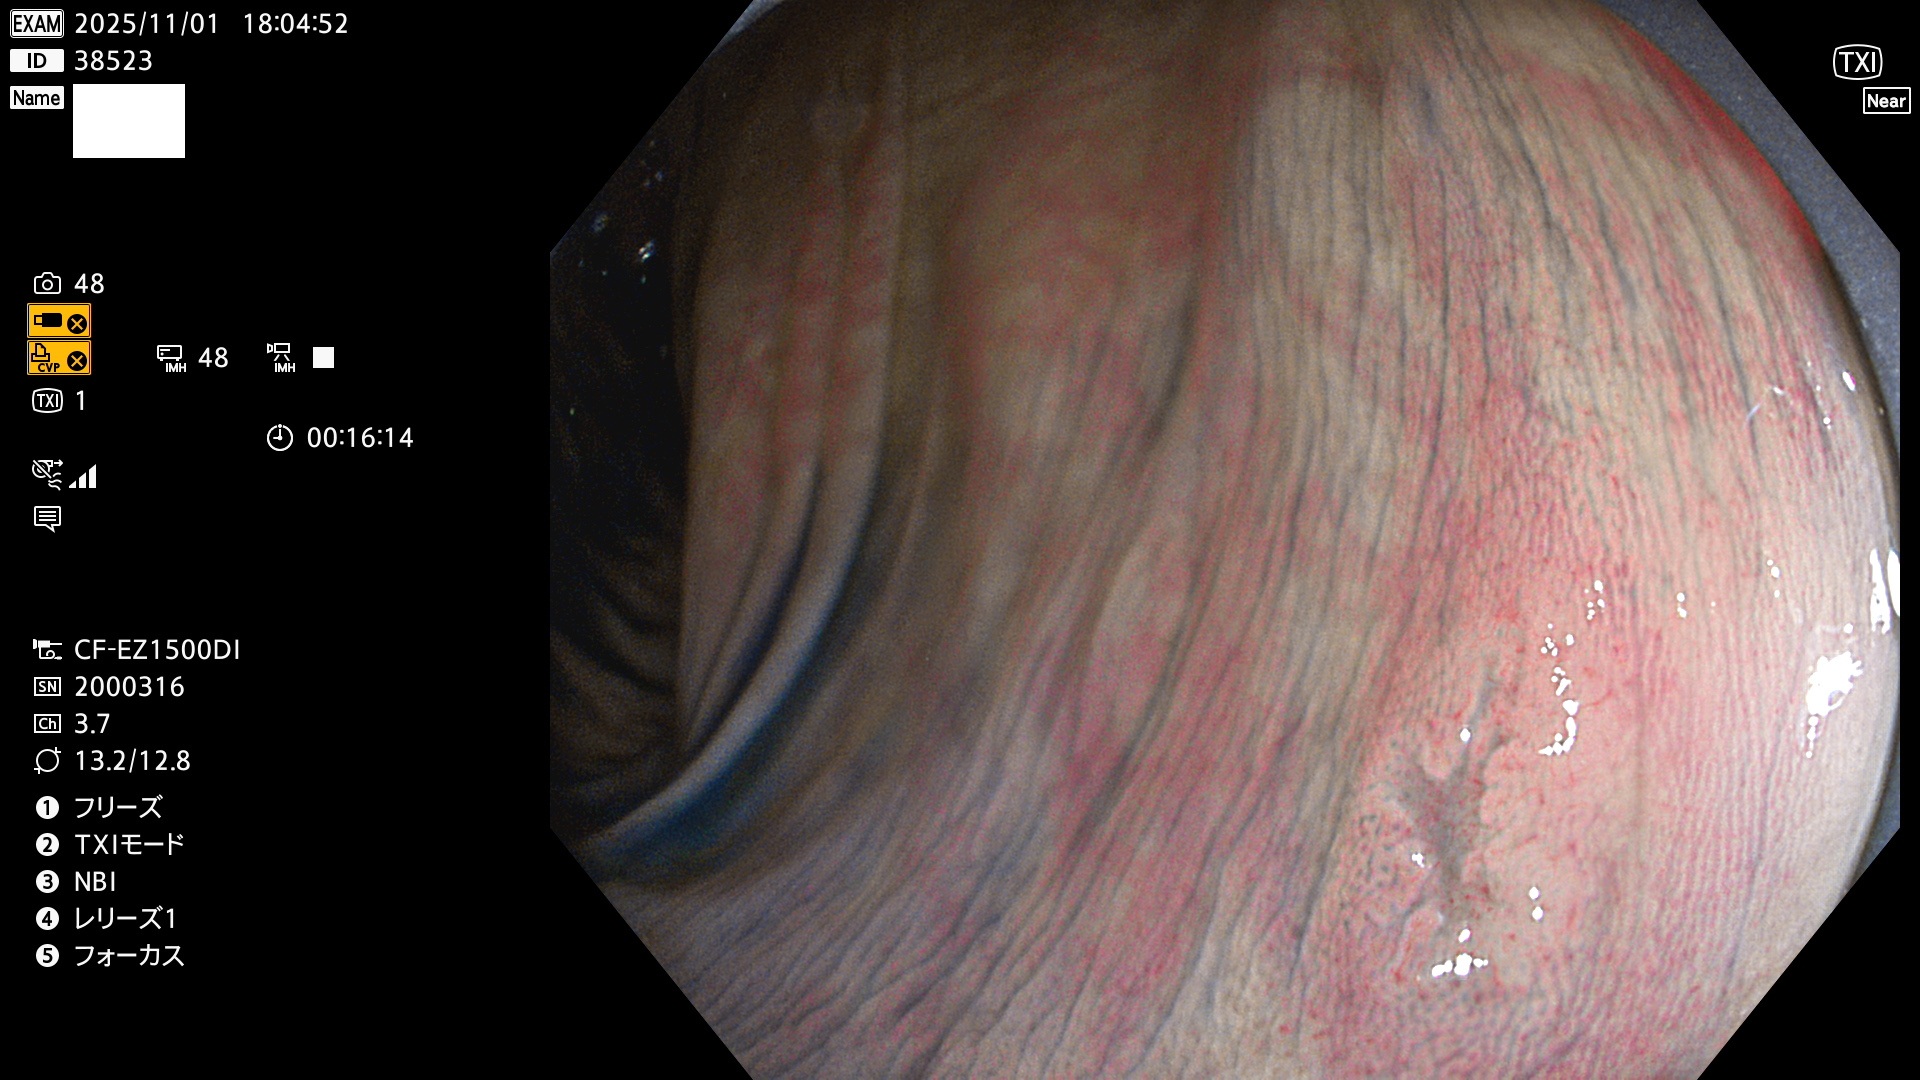

毎週の検査(木・金・土・日)に発見されたUbとUc型・腺腫を、その週の日曜の夜にUPし1週間、提示します。

写真公開の目的は「透明性・信憑性の担保」ですが、公開を希望されない方はメールで御連絡下さい。直ちに削除いたします。

2025年10月30日〜11月2日の4日間(40件)9個 (Uc_ADR=9個/40人=23%)